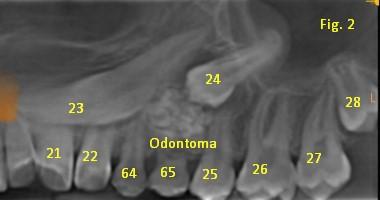

La presentación de casos radiográficos, permite la visualización de patologías que son muy difíciles de ver en la clínica, ya que muchos de ellos son hallazgos radiográficos. Además permite ver y refrescar clasificaciones y conceptos muchas veces estudiados. La presentación de los mismos no incluyen datos personales, mas que edad y sexo, que suelen ser importantes para ver la correlación entre la patología, su aparición o forma de presentación.

Esto también refleja las patologías que aquejan a los pacientes de nuestra región, y trata de ser un faro tanto para profesionales como alumnos que estudian dichas lesiones.